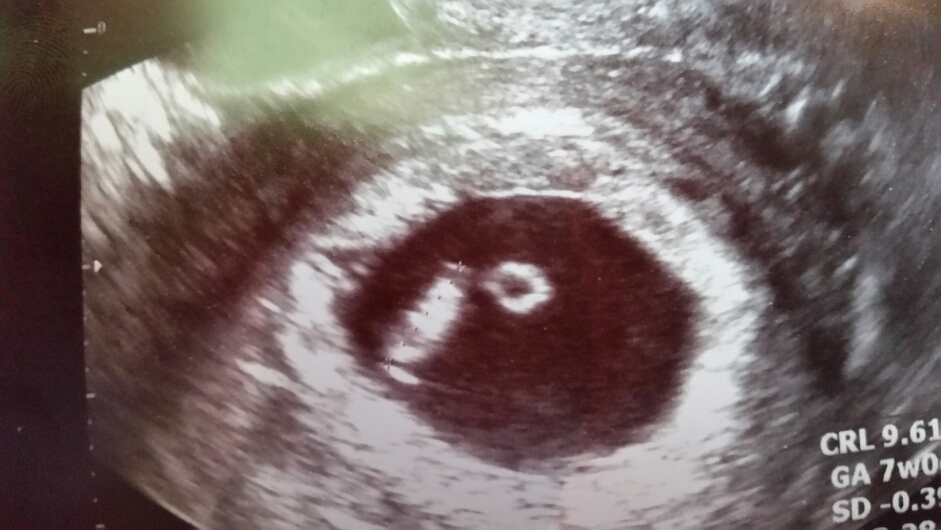

Liitteet

• ImageUploadedByVau Foorumi1447160745.710697.jpg

ImageUploadedByVau Foorumi1447160745.710697.jpg

29.6 KB · Katsottu: 178